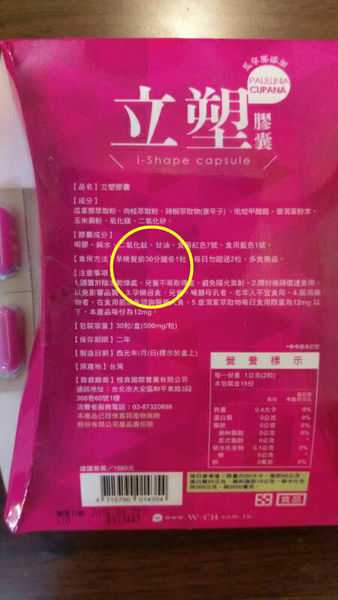

Supercut塑魔纖立塑膠囊的成分有:瓜拿那萃取粉、肉桂萃取粉、辣椒萃取物(唐辛子)、吡啶甲酸鉻、番瀉葉粉末、玉米澱粉、氧化鎂、二氧化矽。

之前上過相關課程,成分表是依照每項成分的多寡來排列順序,排在最前面的就是產品的主要成分!

食用方式:早晚餐前30分鐘各1粒,每日不超過2粒。(多食無益)

包裝是桃紅色的

番瀉葉萃取物每日食用限量為12mg以下,